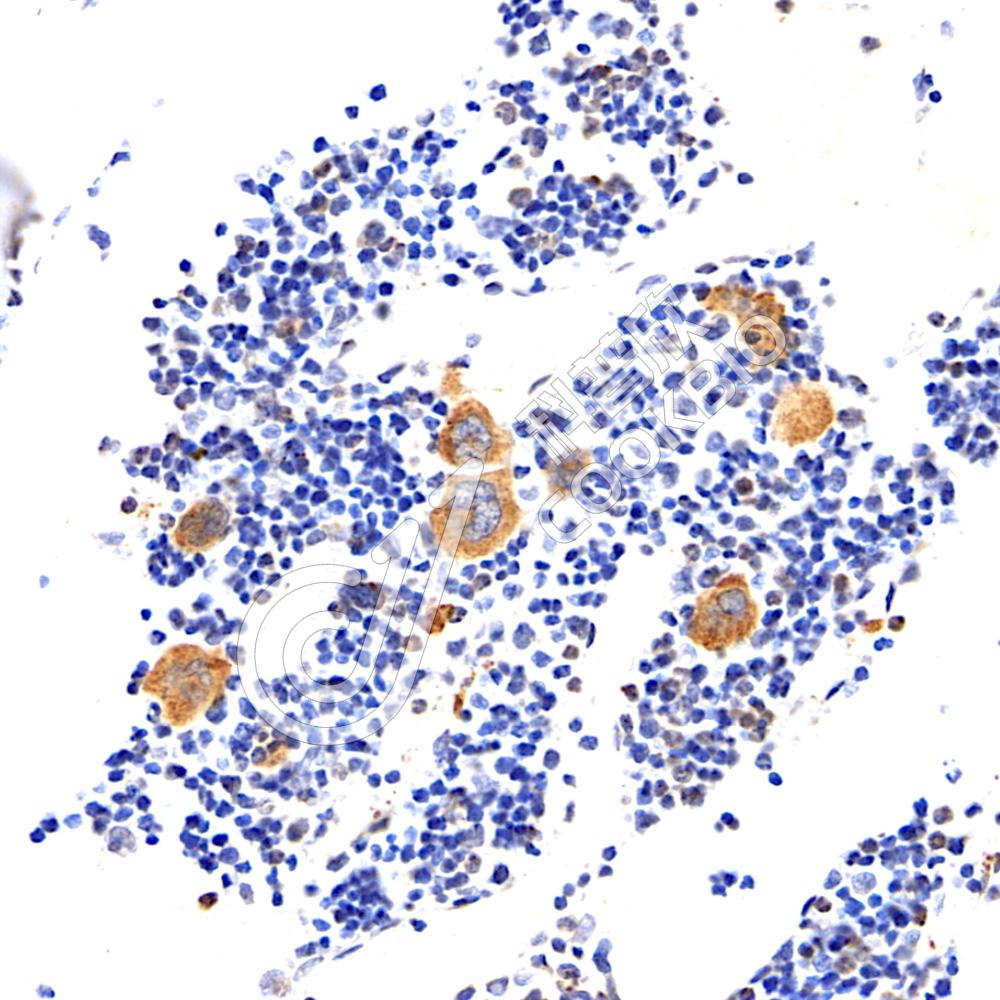

IHC检测LEF1蛋白(货号 K1335661).

样品: 小鼠胸腺, 4%多聚甲醛 (货号KSG1101) 固定12-24小时.

抗原修复: 柠檬酸抗原修复液(干粉, pH 6.0) (KSG1201), 98℃, 20分钟.

—抗: 1: 1200稀释, 4℃ 孵育过夜.

二抗: S-vision免疫组化多聚二抗(山羊抗兔),即用型 (货号KB3906), 室温孵育20分钟.

样品: 大鼠胸腺, 4%多聚甲醛 (货号KSG1101) 固定12-24小时.